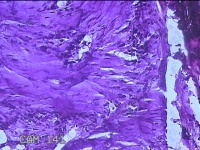

右侧中指尺侧包块

性别

女

年龄

53岁

临床诊断

肌腱腱鞘囊肿

一般病史

发现右侧中指尺侧一包块1年余,无明显疼痛及不适。

标本名称

大体所见

灰白暗红色肿物1.2x0.8x0.3cm一个,表面糜烂,切面灰白粉红色,质软。